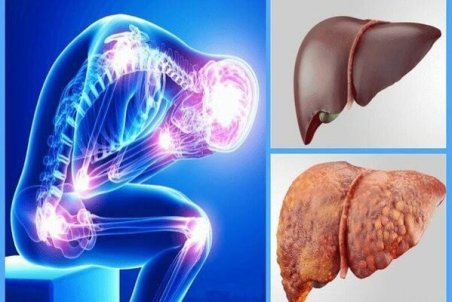

زنگ خطر بروز کبد چرب در جامعه

دبیر علمی چهلوپنجمین همایش سالانه جامعه جراحان ایران با هشدار نسبت به بروز کبد چرب در جامعه گفت: اکنون هیچ دارویی برای جلوگیری و کنترل این عارضه کبدی در ایران و جهان وجود ندارد و داروها در قالب مکملهای دارویی یا گیاهی تجویز میشود

راه های پیشگیری از کبد چرب + عوامل و درمان

برای درمان کبد توصیههایی وجود دارد که با تغییر در سبک زندگی و تغییر رژیم غذایی میتوانید به پیشگیری و درمان کبد چرب کمک کنید. در این مقاله به شما روش های درمان کبد چرب را بهشما میگوییم، میگوییم کبد چرب چیست، علت کبد چرب چیست و چگونه میتوان از کبد چرب

عوارض کبد چرب چیست؟ + فیلم

یک فوق تخصص گوارش در ارتباط با عوارض کبد چرب، نکاتی را مطرح کرده است.

اصلیترین دلایل بروز کبد چرب

متخصصان انگلیسی میگویند عوامل مختلف باعث بروز بیماری کبد چرب میشود.

مهمترین علامت «کبد چرب» چیست؟

یک فوق تخصص گوارش و کبد در رابطه با بیماری «کبد چرب» توضیحاتی ارائه کرده است.

پیوند؛ پایانی تلخ برای بیماران مبتلا به کبد چرب/ سلامت دستگاه تصفیه بدن را چگونه تضمین کنیم؟

متخصصان معتقدند که هیچ درمانی برای کبد چرب وجود ندارد اما با اصلاح سبک زندگی و تغذیه و مداومت بر پیاده روی، می توان از ابتلا به این عارضه پیشگیری کرد.

کبد چرب در زنان؛ این نشانهها را جدی بگیرید

با توجه به تغییر در سبک زندگی انسانها و افزایش استرس و بیتحرکی، بیماریهای زیادی گریبانگیر انسانها شده است. یکی از این بیماریها کبد چرب است که از هر ۱۰ ایرانی سه نفر به آن مبتلا هستند. در این مطلب، قصد داریم به این بیماری بپردازیم.

با این نشانهها شما کبد چرب دارید

بیماری کبد چرب به معنی انباشت چربی در سلولهای کبد بوده البته طبیعی است که چربی در کبد داشته باشید، اما وقتی که چربی بیش از ۵ تا ۱۰ درصد در کبد وجود داشته باشد، در این صورت فرد به بیماری کبد چرب مبتلاست.